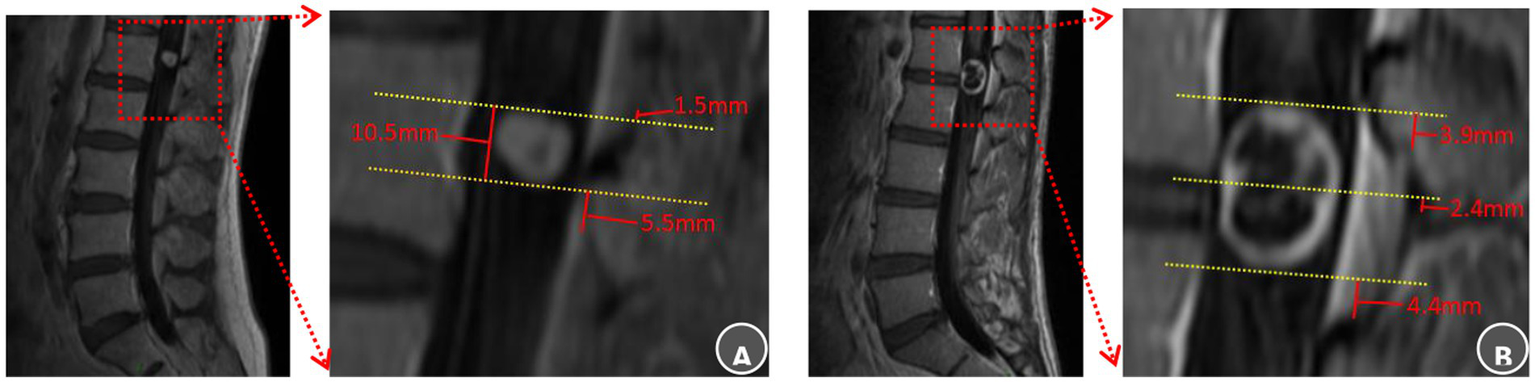

Two senior attending surgeons independently performed all radiological evaluations using the CareStream PACS system (Centricity, GE Healthcare). Preoperative magnetic resonance imaging (MRI) was analyzed to identify the optimal bony landmark for surgical planning. This involved determining the spatial relationships between the tumor’s superior pole, inferior pole, or geometric midpoint and the nearest superior or inferior edge of the lamina. The measurement protocol on sagittal MRI was as follows: Lines were drawn parallel to the adjacent vertebral endplates to establish a consistent plane of reference. The vertical distance from each tumor reference point (superior pole, inferior pole, or midpoint) to the selected bony landmark was measured. A positive value denoted a location superior to the bony reference; a negative value denoted an inferior location. This same convention was applied to measure the spatial relationships between the tumor poles and the nearest boundary of the ligamentum flavum or the predefined S-point. Each surgeon performed all measurements in duplicate, and the mean values were used for the final analysis (Figure 2).

Anatomical landmarks of the lamina and ligamentum flavum boundaries selection and radiological evaluation. (A) L1 intraspinal schwannoma: The superior tumor pole was closest to the superior margin of the L1 lamina, recorded as Ts = L1-sup – 1.5 mm, It was also 1.5 mm inferior to the T12 ligamentum flavum (Ts = T12 LF-inf − 1.5 mm). The inferior pole lay 5.5 mm superior to the L1 ligamentum flavum inferior border (Ti = L1 LF-inf + 5.5 mm). The surgical approach was planned using the superior L1 lamina as the cranial guidance. Laminectomy commenced superiority to expose the upper pole and proceeded caudally within two-thirds of the channel diameter to reveal the inferior pole, ensuring preservation of the L1 ligamentum flavum. (B) L1–2 intraspinal schwannoma: The tumor midportion was closest to the L1 lamina inferior margin (Tm = L1-inf + 2.4 mm). The superior pole was 3.9 mm superior to the L1 ligamentum flavum (Ts = L1 LF-sup + 3.9 mm), while the inferior pole was 4.4 mm superior to the L2 ligamentum flavum inferior border (Ti = L2 LF-inf + 4.4 mm). Surgical planning designated the inferior L1 lamina as the midpoint reference. Bone removal began at this point, continued until exposing the L1 ligamentum flavum superior boundary with an additional 5 mm resection, and extended caudally only to the L1 ligamentum flavum inferior border.